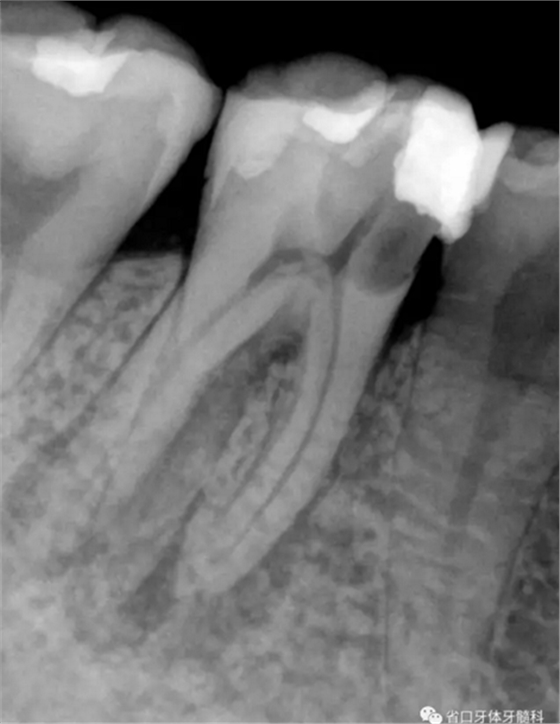

圖1 術前X線片:46/近中根面繼發(fā)齲,根尖周低密度影,遠中舌側根管影像模糊;根分叉低密度影,近中牙槽骨見少許角形吸收。